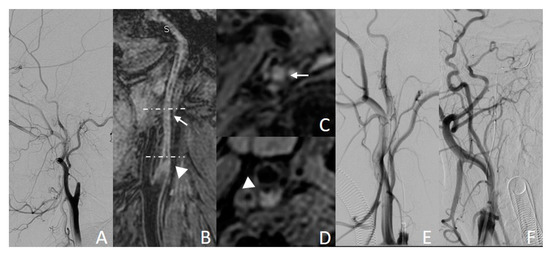

3.3.2. Example Case 2